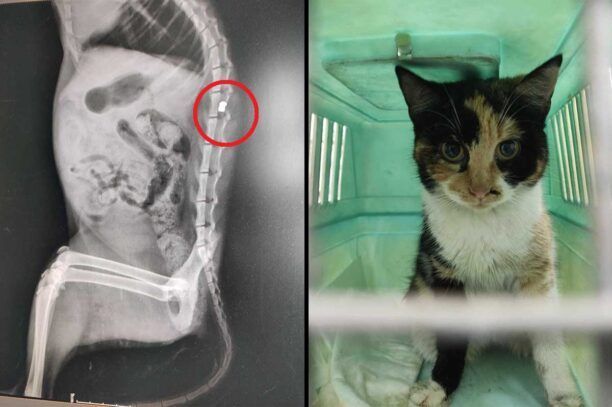

Η ακτινογραφία έδειξε το σφαιρίδιο του αεροβόλο στην σπονδυλική στήλη του ζώου και ίσως η χειρουργική επέμβαση βοηθήσει τη γάτα να ξαναπερπατήσει, εντούτοις χρήματα για αυτό δεν υπάρχουν και απαιτείται να βρεθούν άμεσα ώστε να μην καθηλωθεί ανάπηρο για μια ζωή και αυτό το πλάσμα.

To ζώο βρέθηκε παράλυτο στα πίσω πόδια...

Λοιπόν η γατούλα θα μείνει απ'οτι φαίνεται παράλυτη σαν πρώτη διάγνωση, αν καταφέρουμε και μαζέψουμε λεφτά ίσως να καταφέρει να κάνει χειρουργείο χωρίς να γνωρίζουμε αν θα πετύχει ή όχι. Σε πρώτη φαση ψάχνουμε κάποιον κάποια κάποιους να την υιοθετήσουν ή έστω προσωρινή φιλοξενία μέχρι να βρεθεί ένα παντοτινό σπίτι. Την Παρασκευή θα την πάρω από το κτηνιατρείο και δεν έχω που να την πάω.